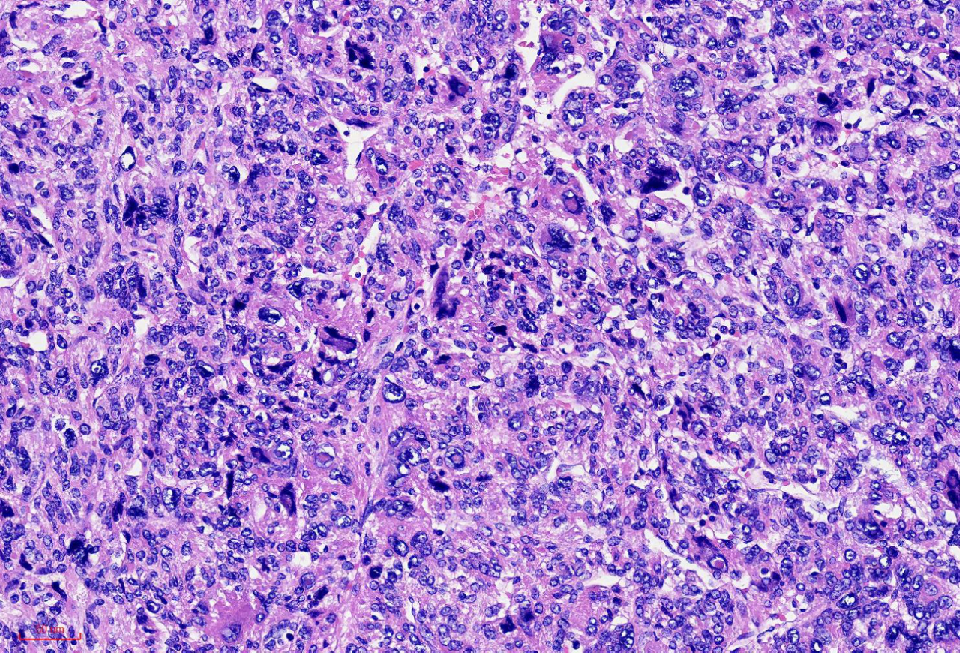

组织学改变

肿瘤与周围境界清楚

肿瘤细胞丰富

瘤细胞排列呈血管外皮瘤样

瘤细胞疏密相间

异型明显,可见核内包涵体,红核仁

未见凝固性坏死

核分裂象数2个/10HPF

肿瘤境界清楚

细胞丰富

鹿角样/血管外皮瘤样血管

肺水肿样水肿/疏密相间

细胞核奇异,嗜酸性胞质,有显著的嗜酸性核仁,核仁周围可见空晕,部分细胞呈横纹肌样

核分裂象少见

无凝固性坏死